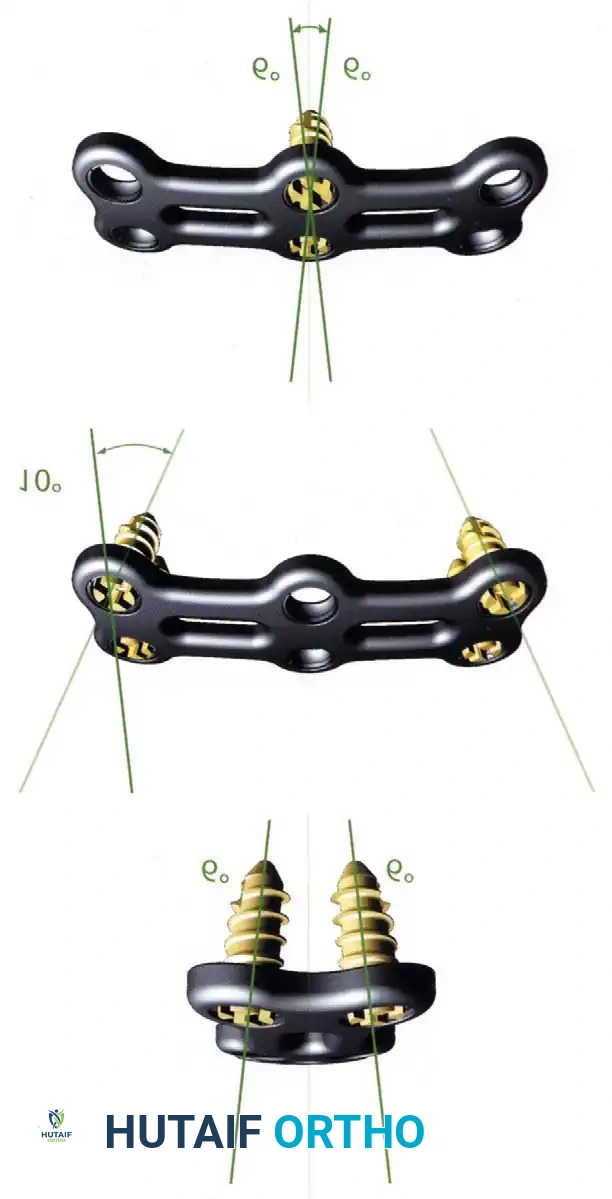

5. Plating: Apply a rigid anterior cervical plate. Ensure screws are placed parallel to the endplates and do not breach the adjacent disc spaces.

Fig 6. Anterior cervical plating construct providing rigid stabilization of the anterior column.